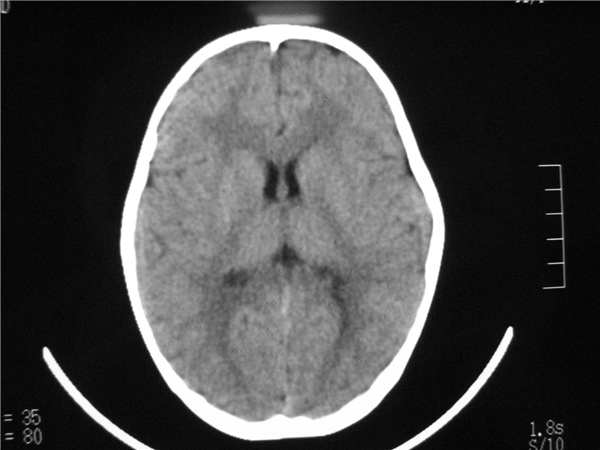

标题: PED2843: CT-23675 F 4Y 大家看看颅内有问题没。 [打印本页]

标题: PED2843: CT-23675 F 4Y 大家看看颅内有问题没。

未见明显异常。

四脑室扩大,三脑室稍扩大上移

胼胝体发育不全??

六脑室

四脑室扩大,,六脑室

颅脑ct平扫未见异常。

颅脑ct轴位平扫颅内未见明确异常。

四脑室扩大,密度降低,图像的问题?建议mr扫描。